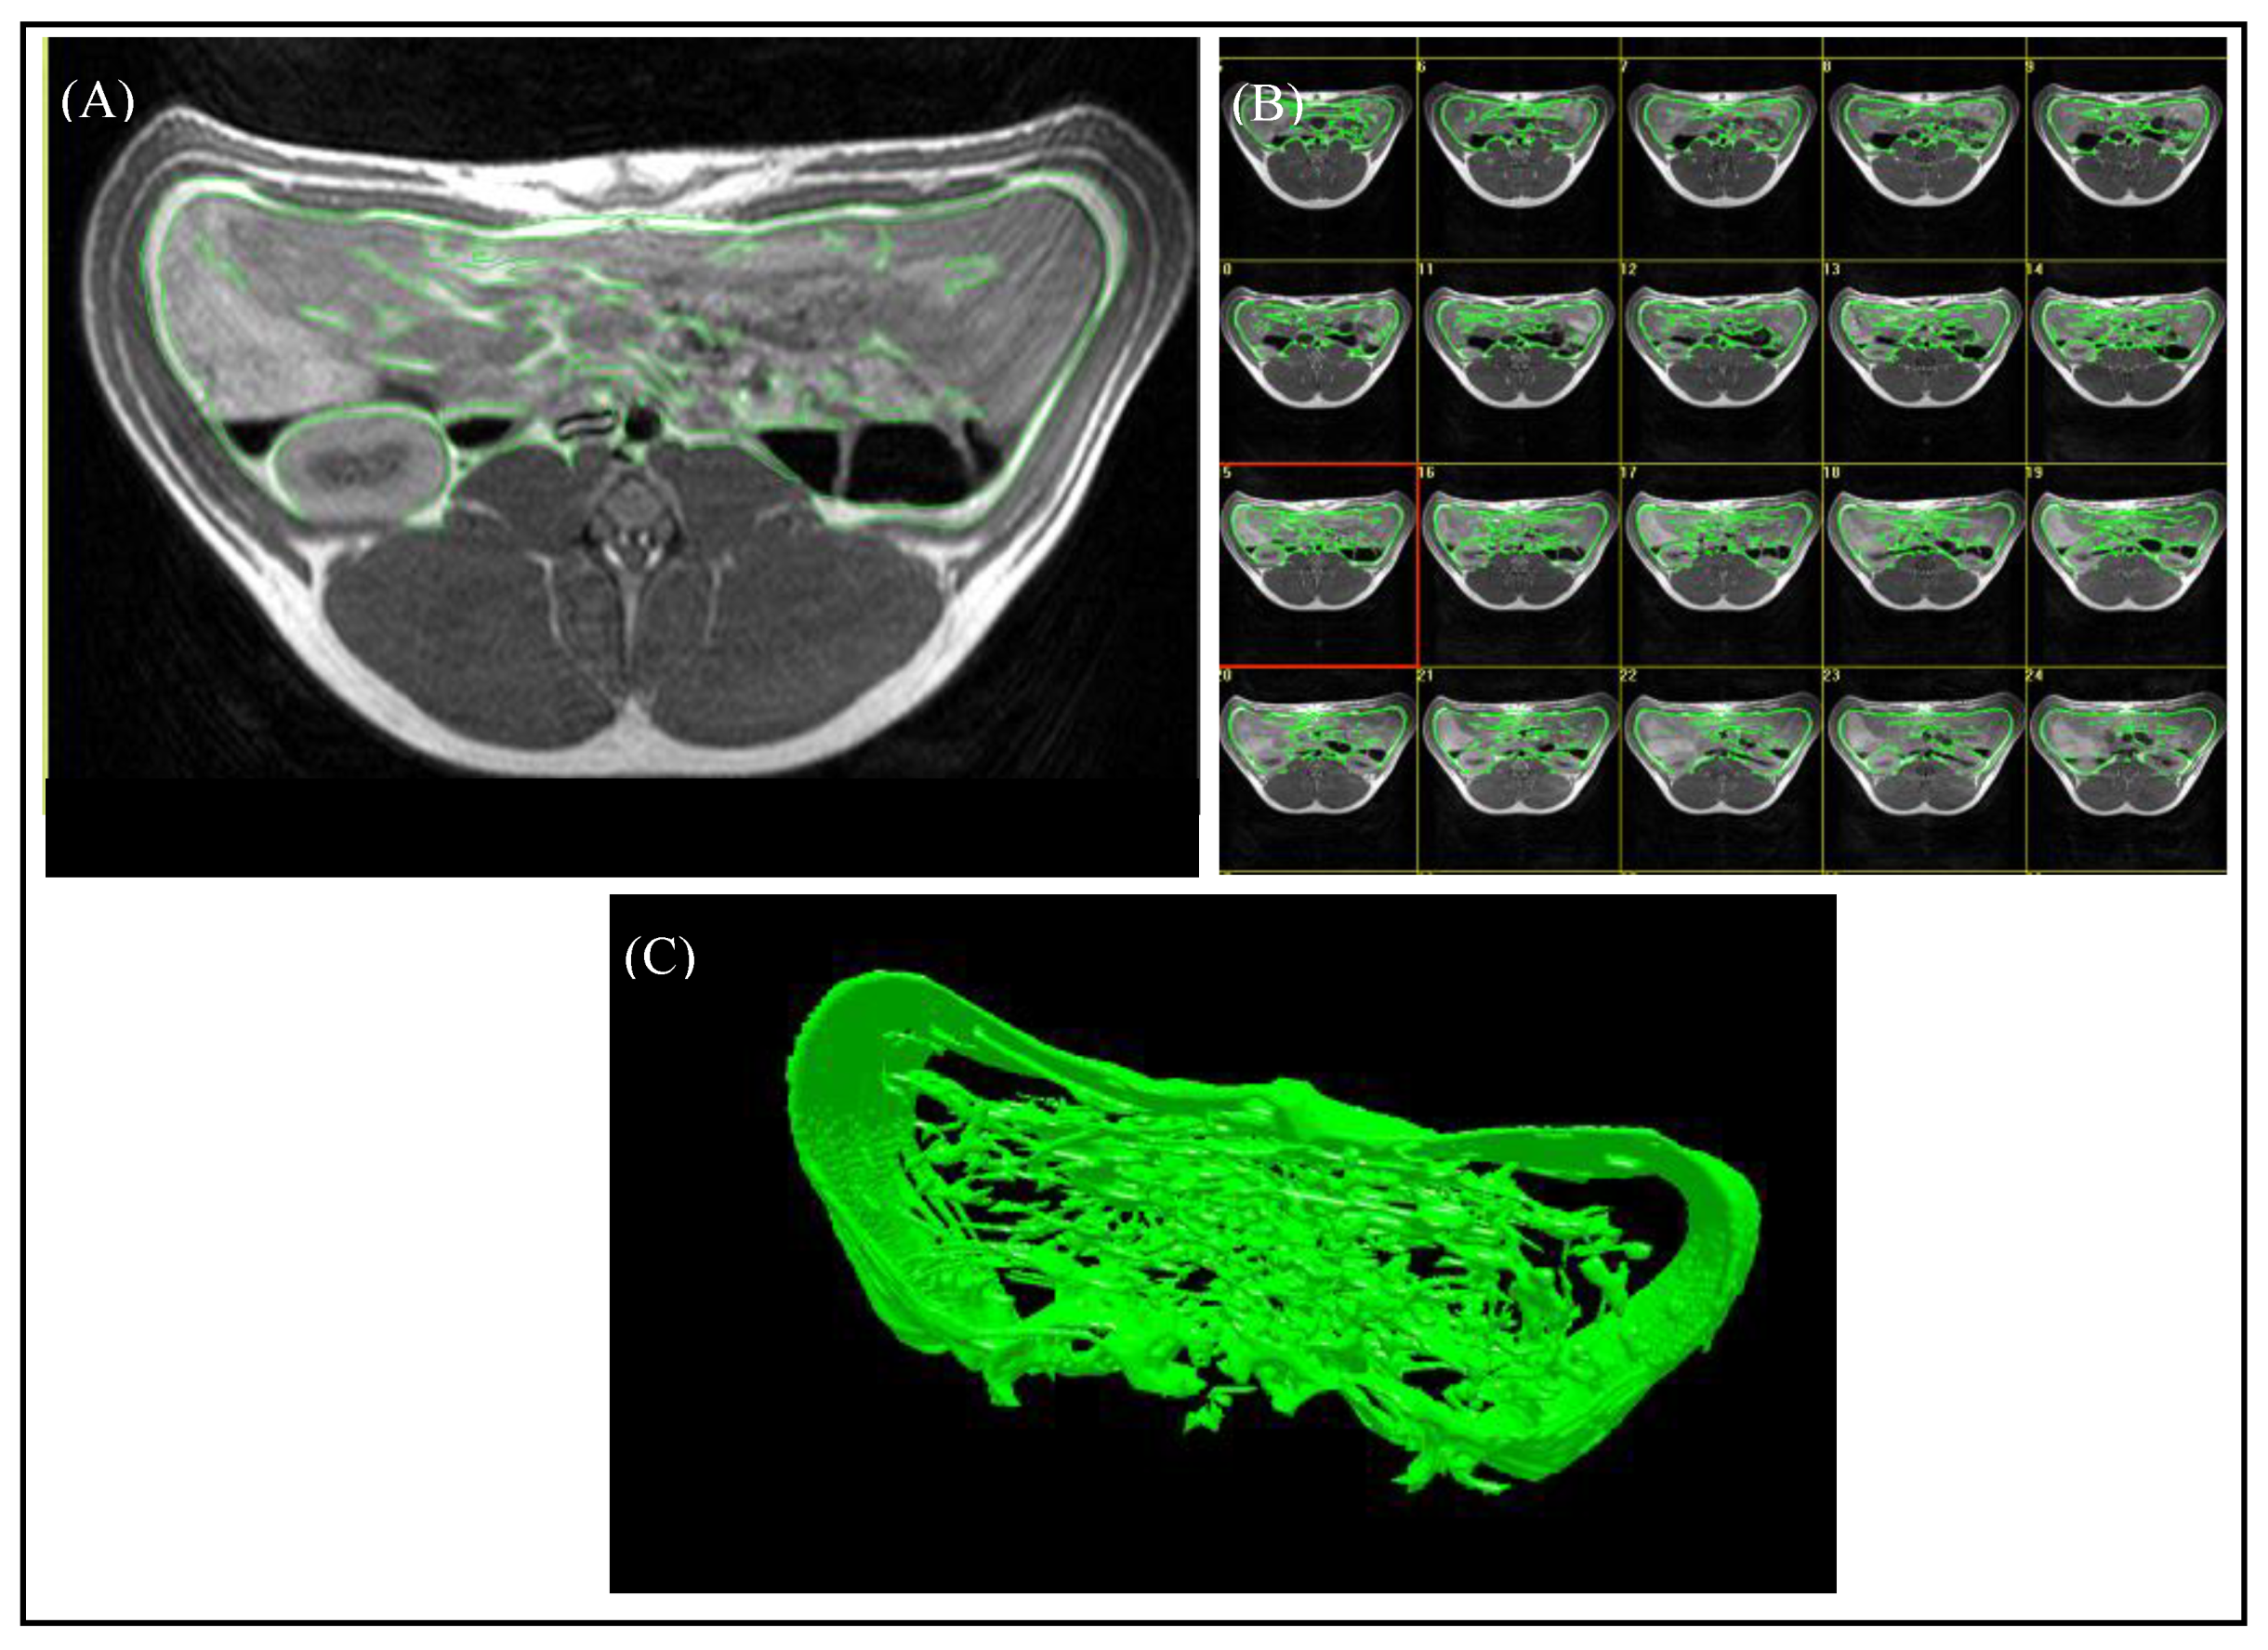

2.2.1. Magnetic Resonance Imaging

2.3.1. MRI Evaluation